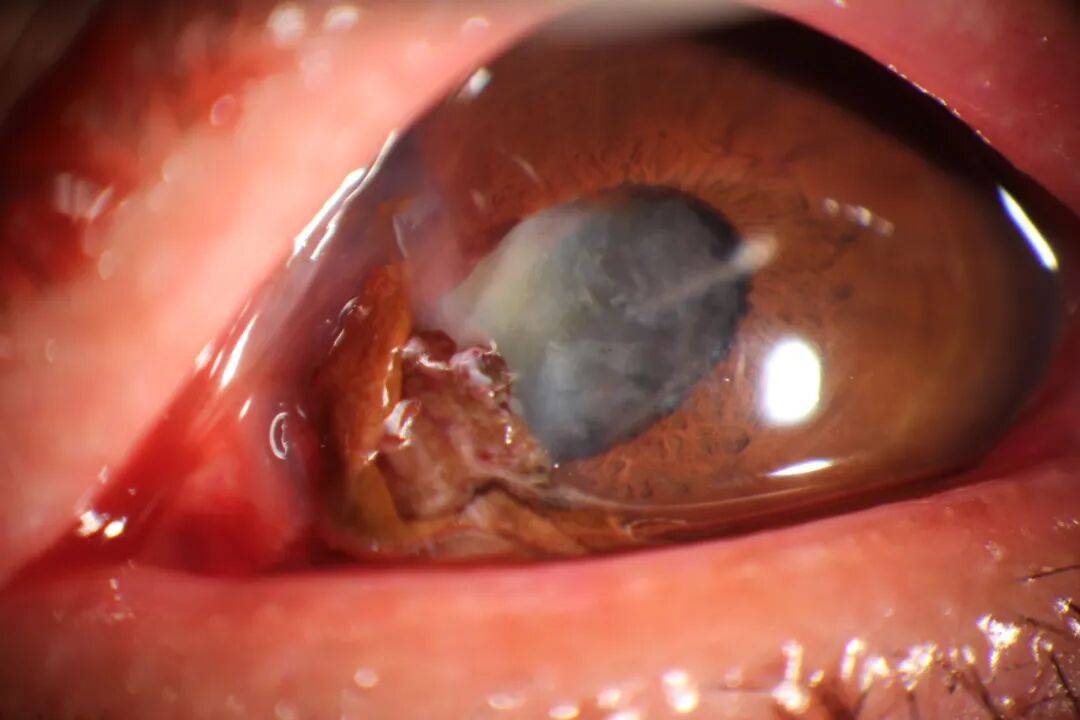

07                     前房积血

多由眼球钝挫伤、眼部手术伤、炎症、肿瘤或药物引起的虹膜血管破裂,导致血液积聚在前房中,少量积血可自行吸收,但若出血量较大,或将引起继发性青光眼。